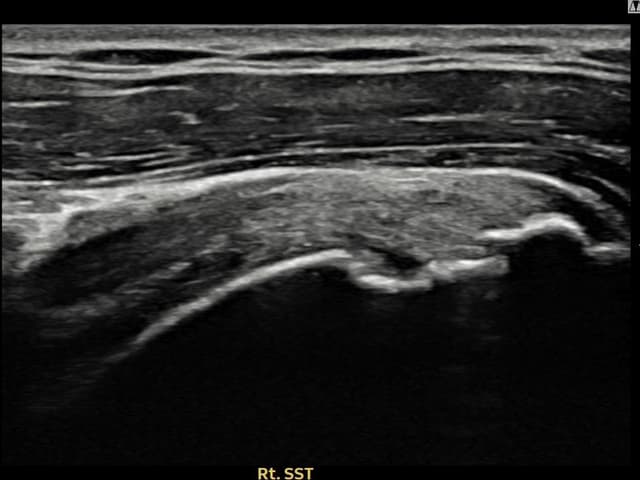

実際の患者様の施術前後の超音波画像。

手術なしで実現できる回復をご確認ください。

[経過期間: 23.07.18~23.09.14]

[縫縮術] 超音波検査にて左 棘上筋腱 광범위 部分断裂(15mm × 6mm (腱厚の約70%欠損))を確認。縫縮術施行後、腱の連続性が回復し、日常生活に復帰されました。